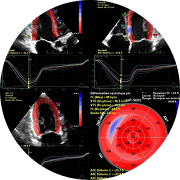

Visualisation précise du cœur et de la circulation sanguine.

Imagerie cardiaque avancée pour un diagnostic détaillé.